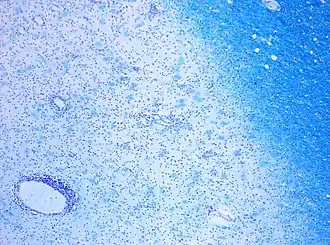

A combination of histologic and/or immunohistochemical stains can be used to visualize post-mortem MS characteristic lesions and to diagnose post-mortem "inflammatory demyelinating lesions consistent with MS":[12]

- hematoxylin and eosin stain (demonstrates tissue and cell morphology)

- myelin stains (Luxol fast blue/periodic acid-Schiff, Luxol fast blue/hematoxylin/eosin, or immunohistochemistry for myelin proteins)

- macrophage-specific markers (immunohistochemistry for KiM1P or CD68)

- stains for axons (Bielschowsky silver impregnation or immunohistochemistry for neurofilament protein)

- stains for astrocytes (hematoxylin and eosin or immunohistochemistry for glial fibrillary acidic protein) and

- stains for the different lymphocyte subtypes (immunohistochemistry for CD3, CD4, CD8, CD20, and/or CD138)

These markers are specific for the different processes that drive the formation of plaques: inflammation, myelin breakdown, astrogliosis, oligodendrocyte injury, neurodegeneration, axonal loss and remyelination. MS lesions evolve differently during early versus chronic disease phases, and within each phase, different kind of activity appears.

The classification system for the lesions was updated in 2017. This system classifies MS lesions as active, mixed active/inactive, or inactive lesions based on the presence and distribution of macrophages/microglia. They locate the slowly expanding lesions inside the mixed subtype and provide a description of the different lesion types and required staining techniques.[13]